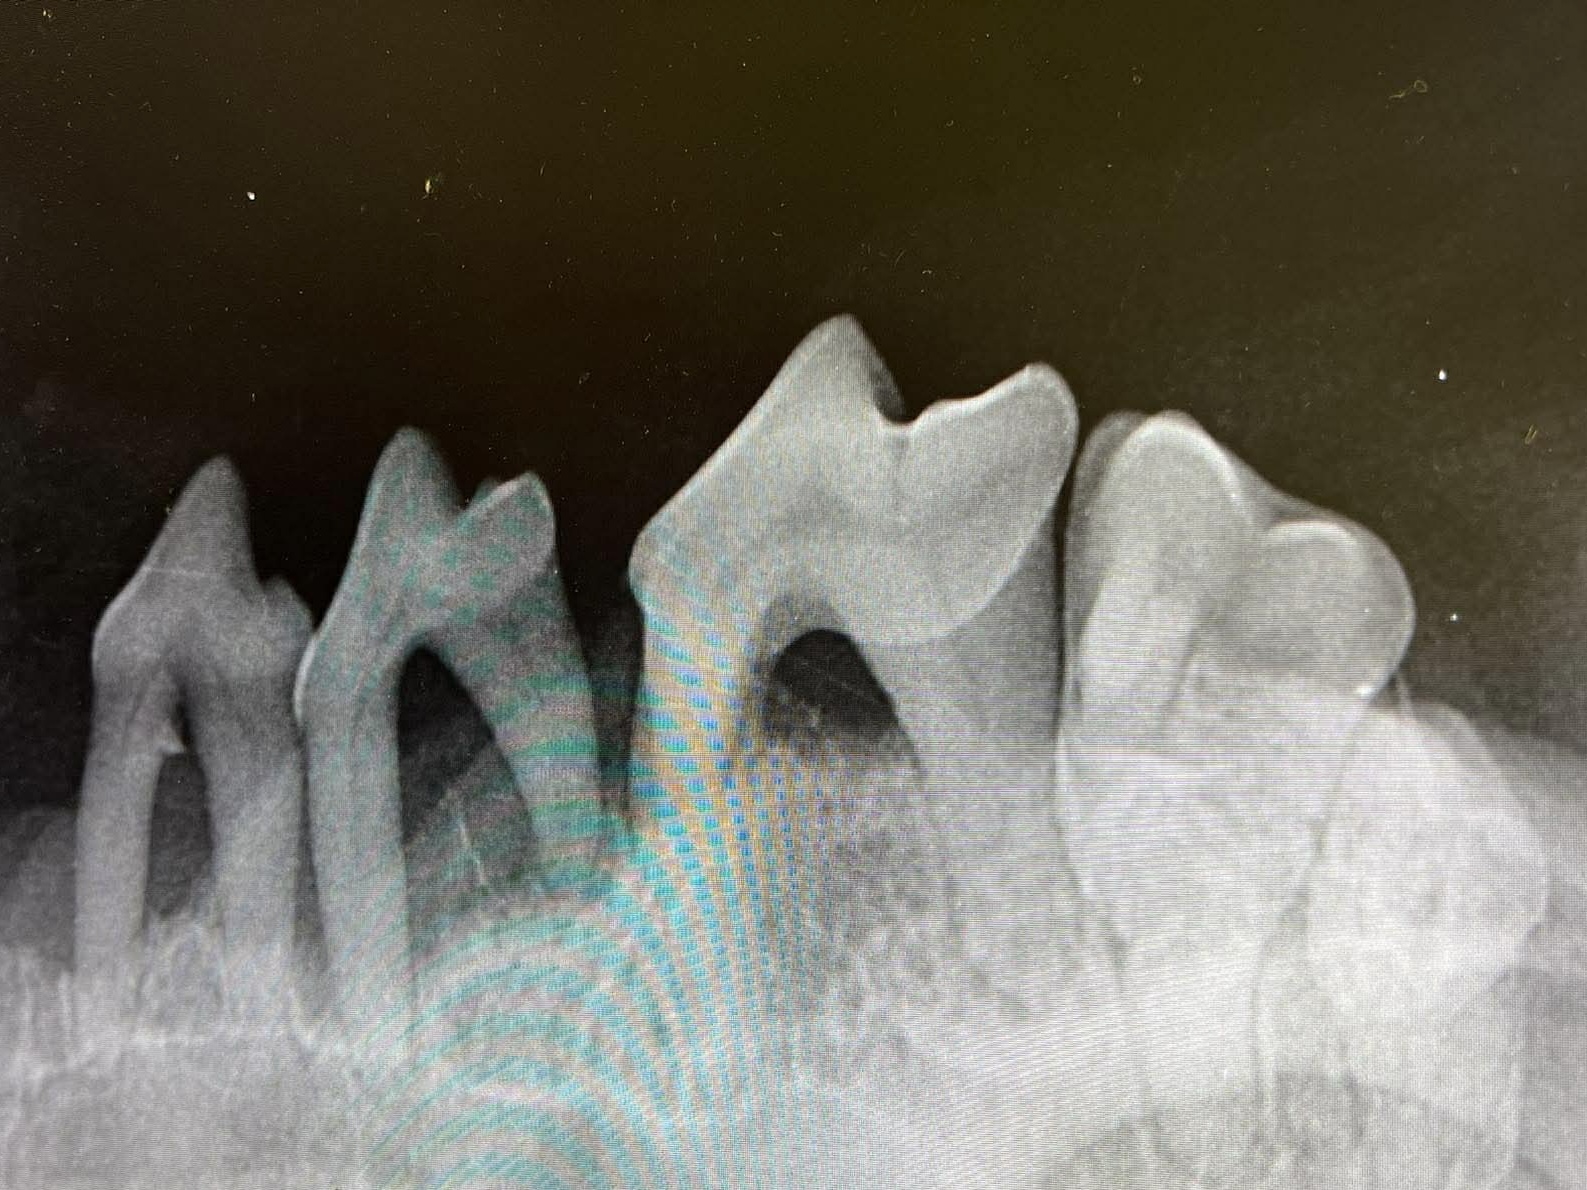

A kutyák és macskák fogait érintő elváltozásai nagyon gyakran előfordulnak a mindennapi állatorvosi praxisokban és nagy veszélyt rejtenek magukban. Ugyanis különböző további betegséget okozhatnak, úgymint a szívbetegséget és veseelégtelenséget. A rendszeres fogápolás kritikus fontosságú kedvence egészsége szempontjából, ehhez kérje állatorvosa tanácsait. Forduljon bizalommal hozzánk, hogy segíthessünk megoldani kedvence fogászati problémáit.

- Fogak sárgák vagy barnák, esetleg mozog vagy hiányzik a fog?